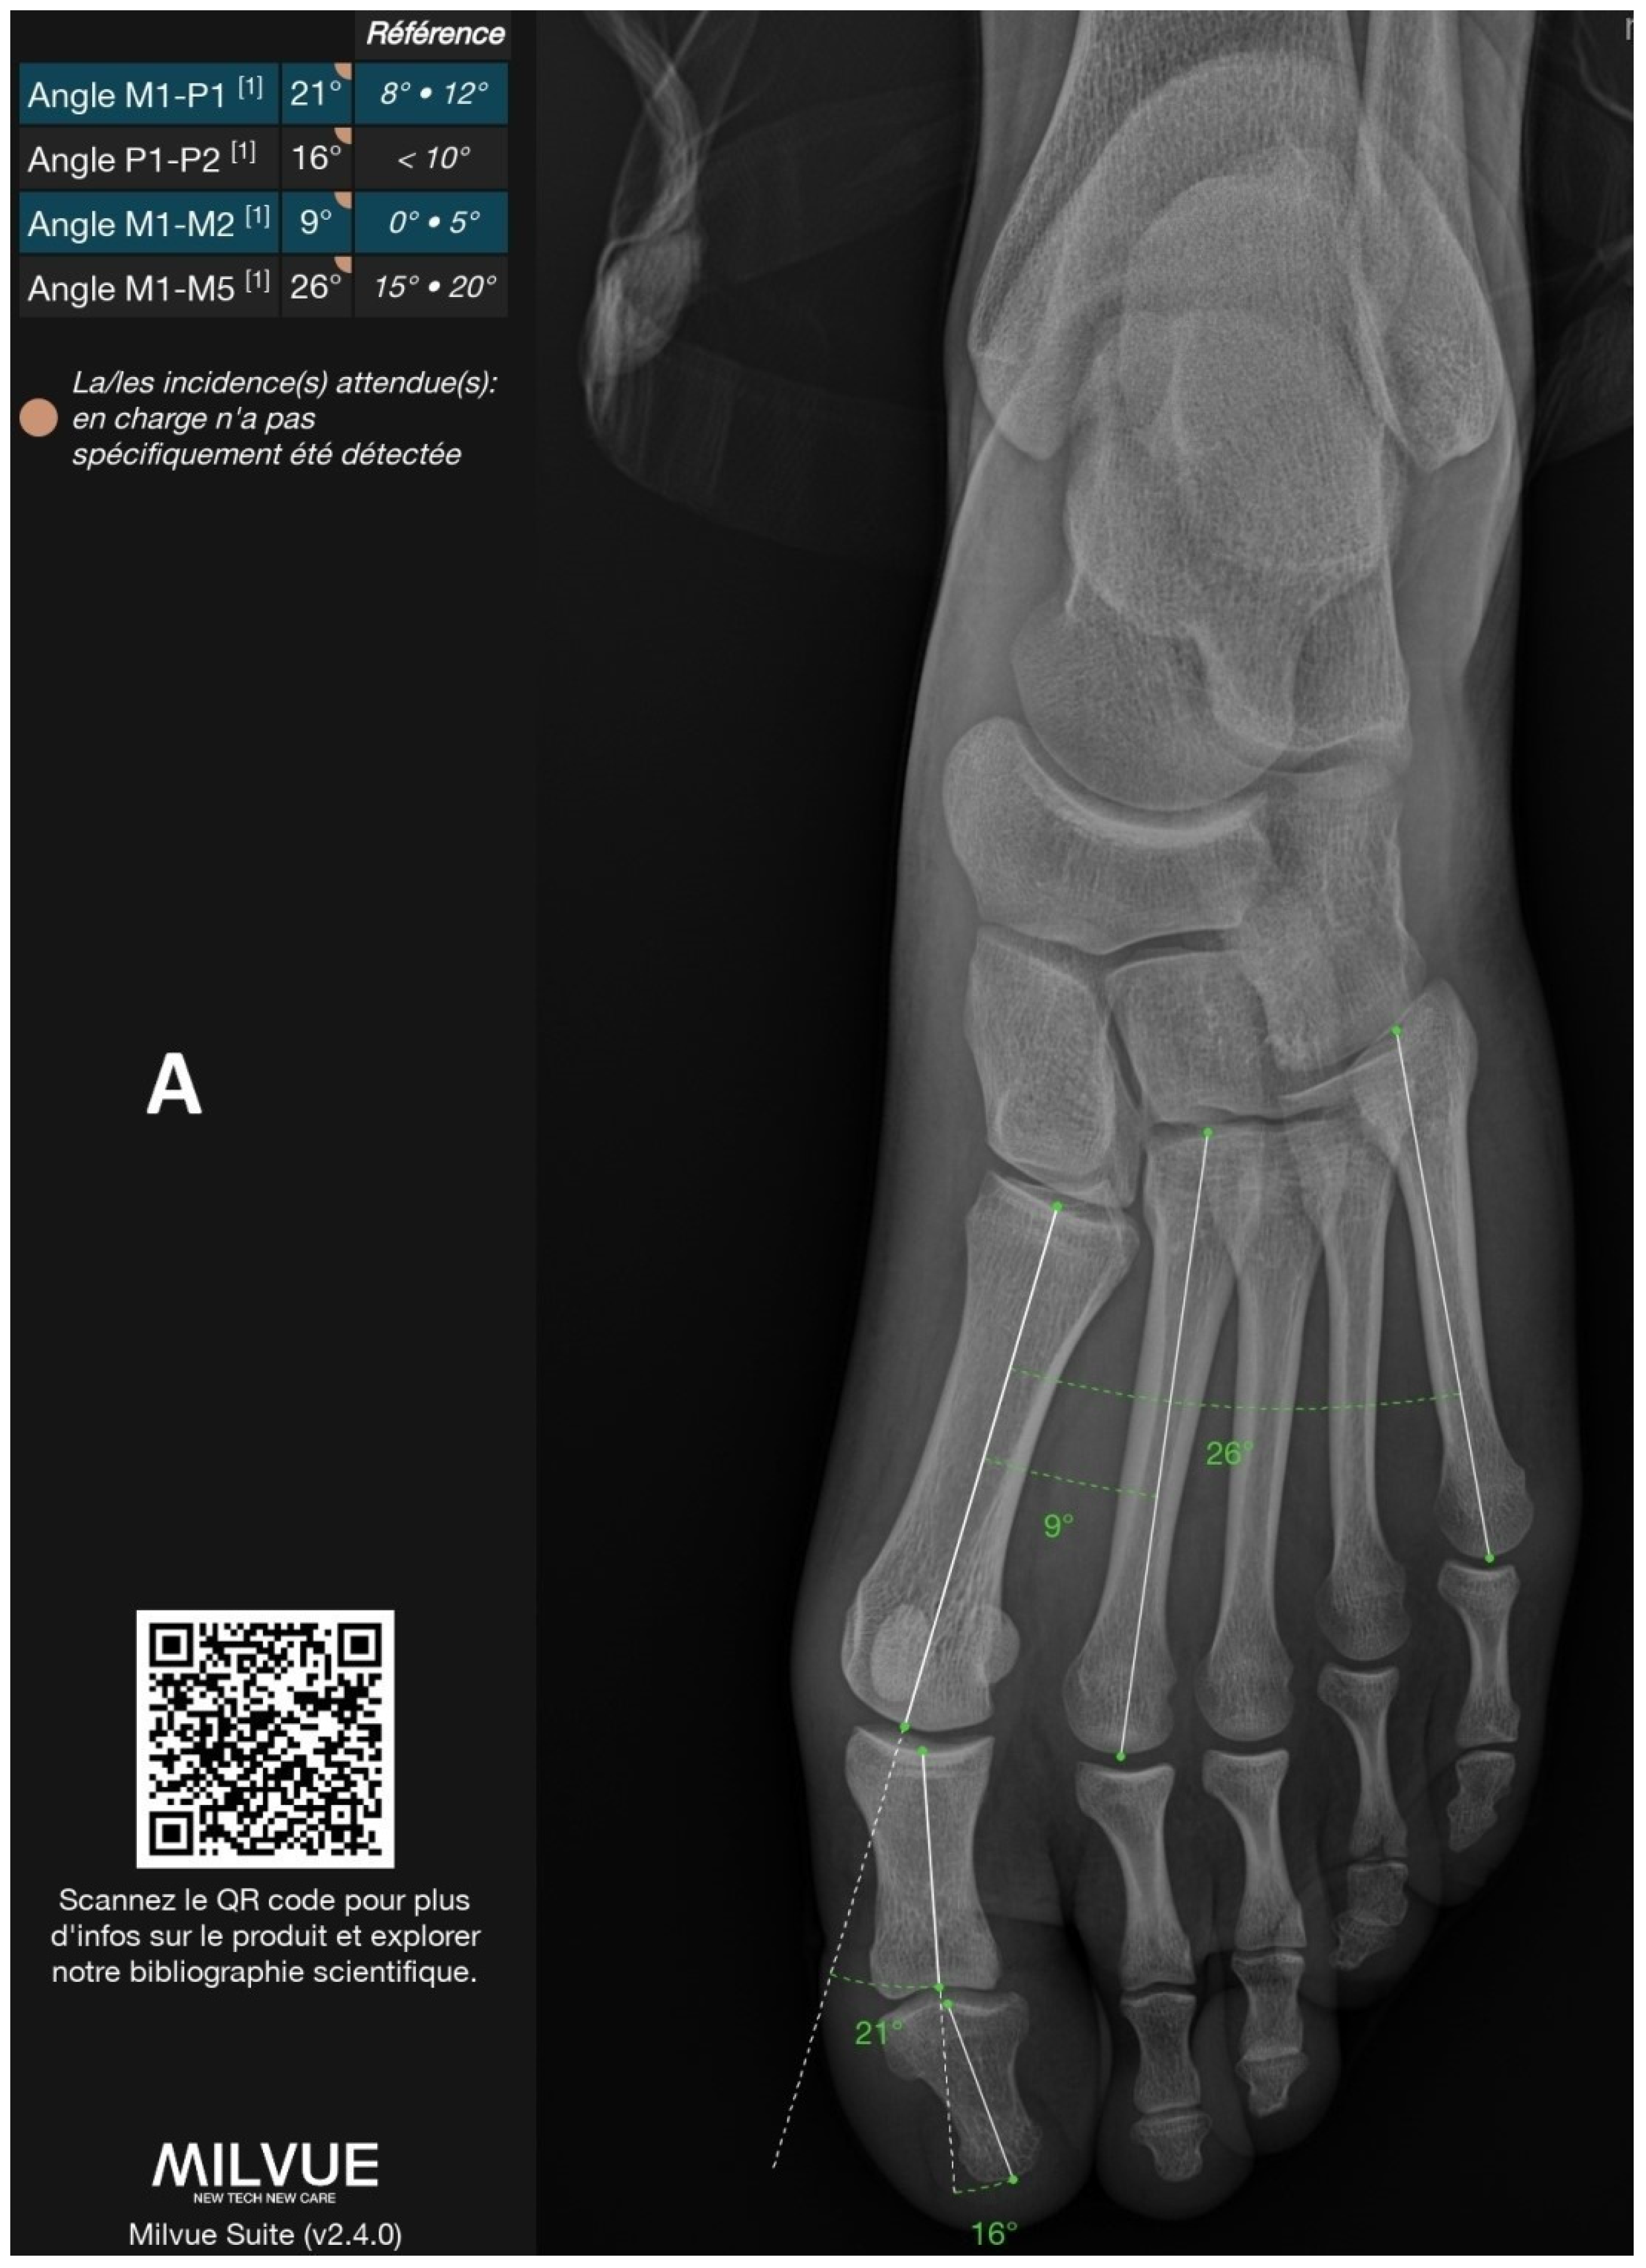

Figure 1 shows an example of a radiograph annotated by the deep learning model, illustrating all automatically detected angles.

Figure 1.

Example of a radiograph analyzed by the deep learning model with all annotated angles. (A): Frontal view. (B): Lateral view. The software output includes a prompt to scan the QR code for more information about the product and to explore related scientific publications, directing to the following URL: https://product.milvue.com/fr/?content=cD1jZSZ2PXYyLjQuMA%3D%3D (accessed on 5 June 2025).